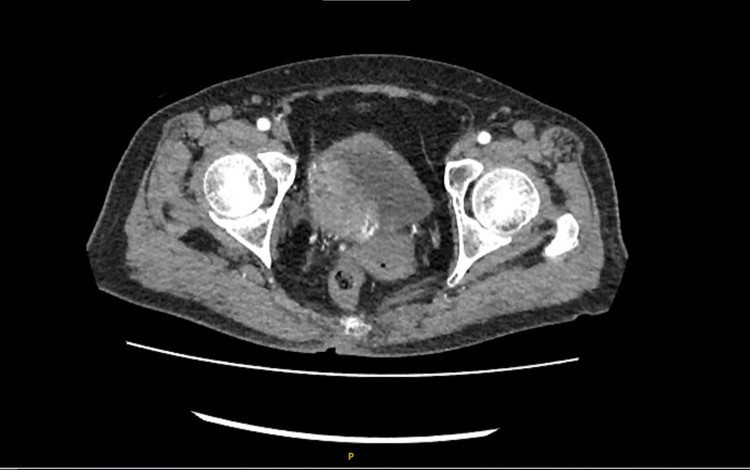

Qua khám lâm sàng và các khảo sát hình ảnh bằng soi bàng quang và chụp MSCT, các bác sĩ xác định nhiều khối u rải rác khắp bàng quang, bướu to nhất thành trái bàng quang có kích thước 3cm, xâm lấn niệu quản phải, thận phải ứ nước độ II cách miệng niệu quản trái gần 5mm, thận phải ứ nước độ II.

Dựa trên kết quả cận lâm sàng, bác sĩ chẩn đoán bệnh nhân bị bướu bàng quang trên nền bệnh tăng huyết áp, rối loạn lipid máu, đái tháo đường type 2.

| Hình ảnh tình trạng bệnh của bệnh nhân trên phim chụp |